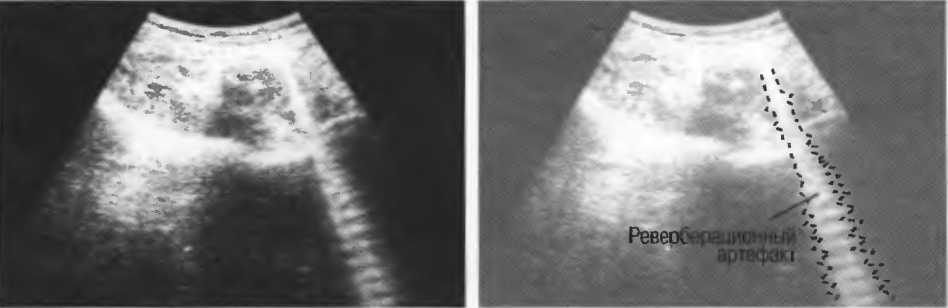

Реверберации

Реверберации имеют место при прохождении ультразвукового луча от одного вида ткани к другому при резко выраженном различии акустического сопротивления этих тканей, например от кишечного газа к печени или ребрам: реверберации могут экранировать ткани, лежащие за газом (рис. 20а).

Реверберации могут полностью менять изображение, создавая линейные структуры или зеркальное отображение. Например, реверберации между параллельными слоями подкожных тканей создают параллельные линейные структуры в мочевом пузыре (рис. 20в).